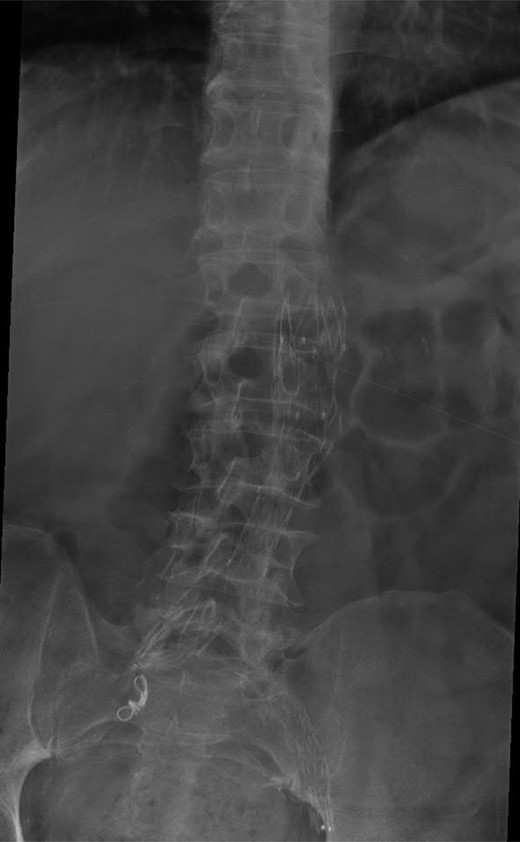

A 74-year-old male was admitted with an intracapsular fractured left neck of femur (Fig. 1). According to the NICE guidelines, he received a cemented THR (Fig. 2) via the posterior approach in the lateral decubitus position. Five weeks prior, he had an EVAR for a leaking AAA. Due to a calcified, narrow right common iliac artery (CIA), the EVAR consisted of a left aortouniiliac endograft with coil embolization of the right CIA and a femoro-femoral crossover graft (Figs 3 and 4).

AP radiograph of the lumbar spine demonstrating the aortouniiliac EVAR with coil embolization of the right CIA.

Lateral radiograph of the lumbar spine demonstrating the aortouniiliac EVAR with coil embolization of the right CIA.